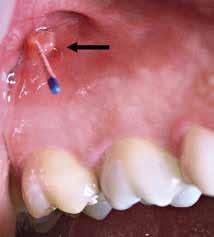

med stor cervikal restaurering facialt (pil) og fistel i den faciale slimhinde ud for første præmolar. B. Røntgenoptagelse viser restaurering i den koronale del (pil) og periapikal læsion under anden præmolar.

Fig. 9. A. Clinical photo of second premolar with large buccal cervical restoration (arrow) and fistula on buccal mucosa below first premolar. B. Radiograph showing restoration in the coronal part (arrow) and periapical lesion under second premolar.